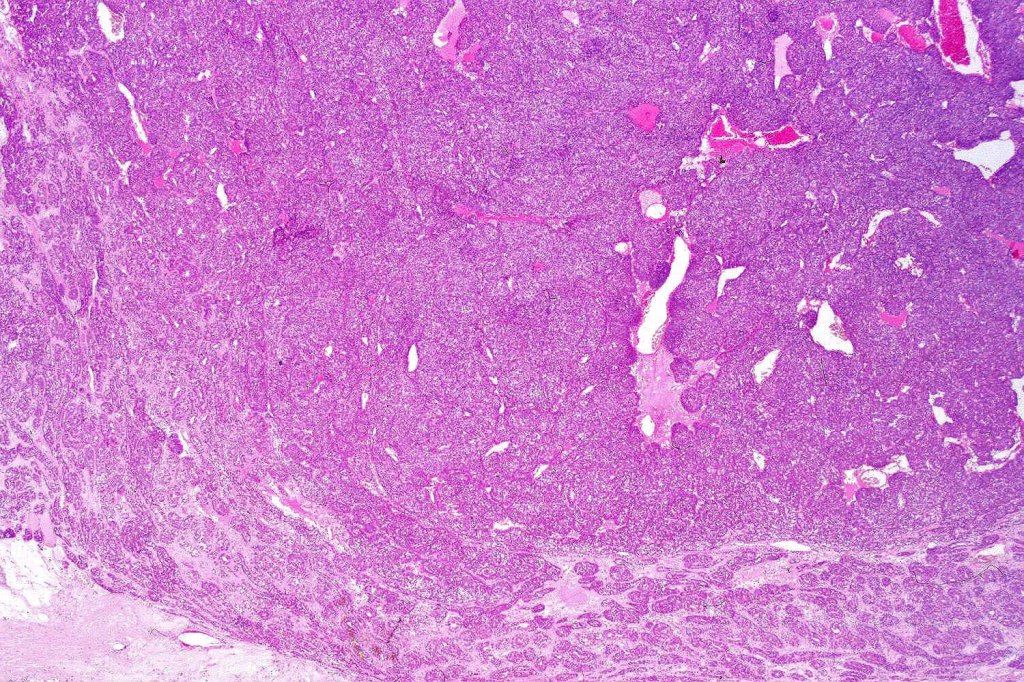

Histological features

•Pre-existent spiradenoma

•Malignant component shows loss of dual cell population, increased mitotic activity, atypical mitoses & necrosis

•Mixed spiradenocylindrocarcinoma